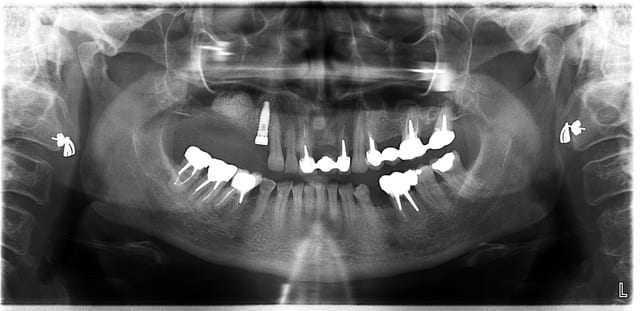

je viens de faire une pano pour contrôler un soulevé tout à l'heure, je le post en PJ car je trouve la définition extra, et il n'y a pas de déformation : l'implant est rectiligne, contrairement à ceux sur la dernière pano que j'ai reçue d'un radiologue il y a 15 jours qui étaient déformés; en plus , le biomat' n'était pas très bien visible, là, il est super

le liseré foncé autour de l'implant est normal, il n'existe pas sur une rétro

au fait, superbe soulevé de sinus , bravo !

merci ;-) c'est toujours rigolo, cette grosse bouboule de futur nonosse dans un sinus;